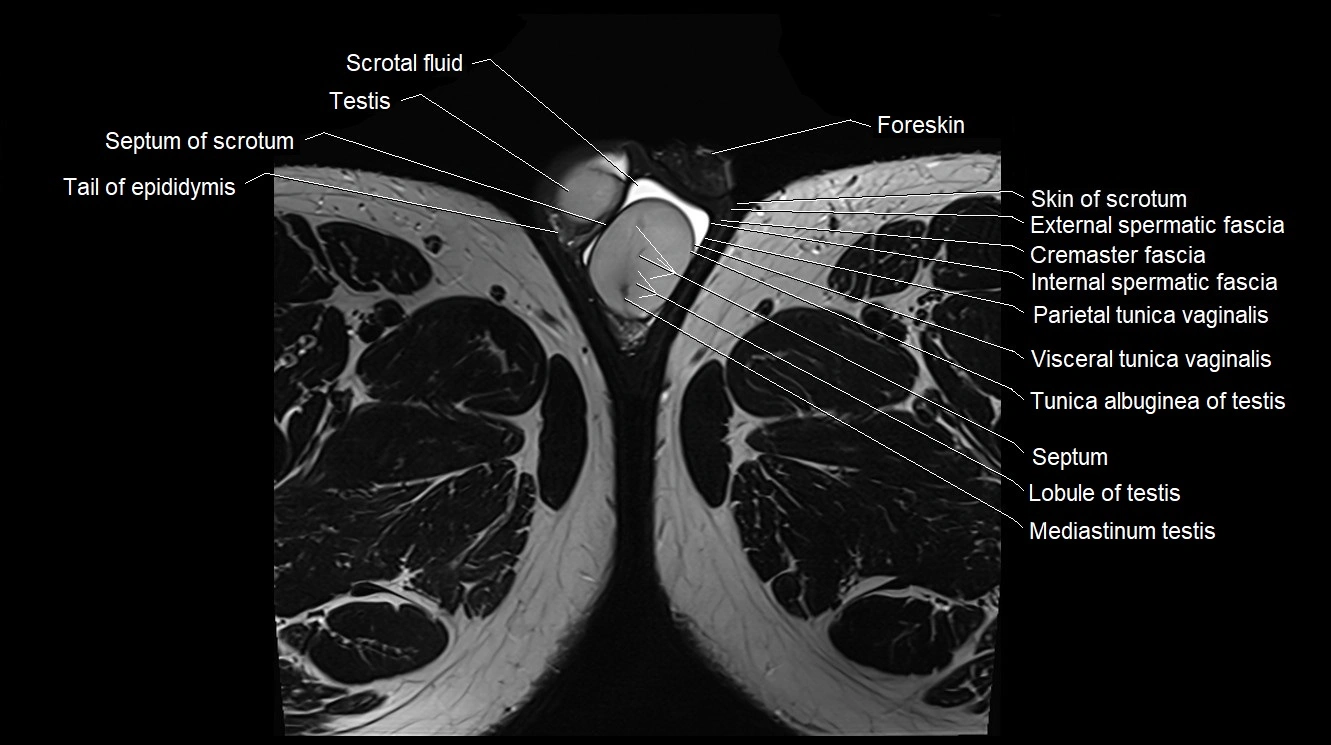

- Cremaster fascia

- External spermatic fascia

- Foreskin

- Internal spermatic fascia

- Lobule of testis

- Mediastinum testis

- Parietal tunica vaginalis

- Scrotal fluid

- Septum of scrotum

- Septum of testis

- Skin of scrotum

- Tail of epididymis

- Testis

- Tunica albuginea of testis

- Visceral tunica vaginalis